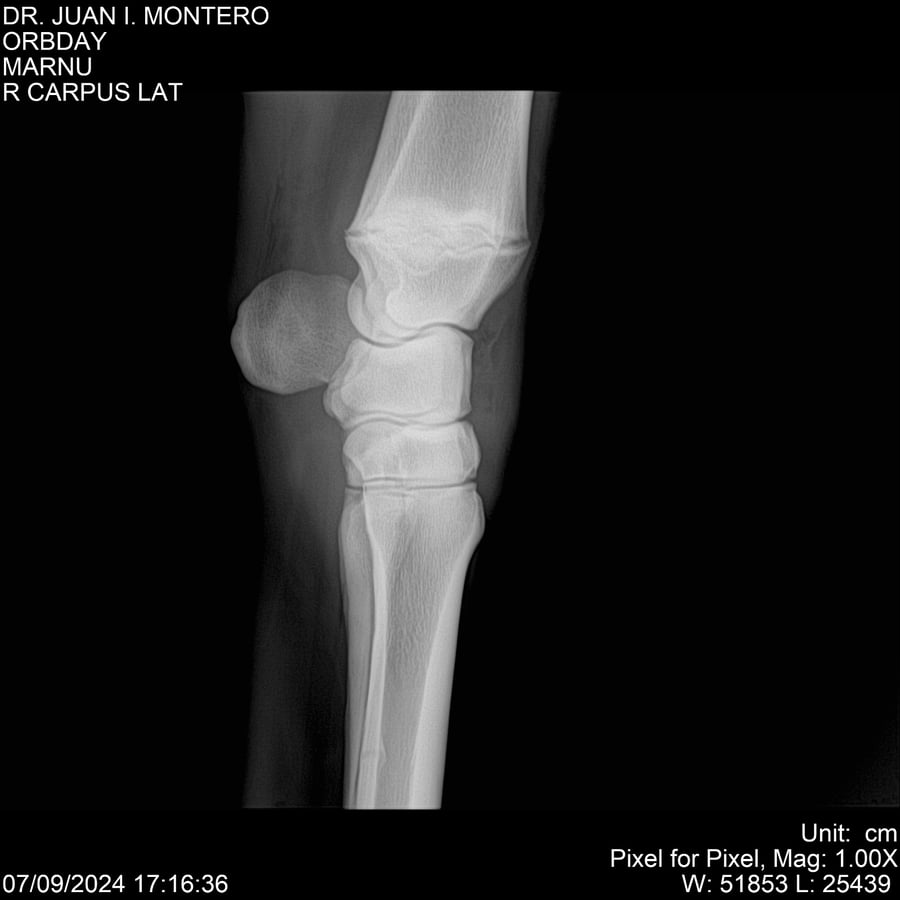

• Empresa: Abelenda N. R., Walter Hugo